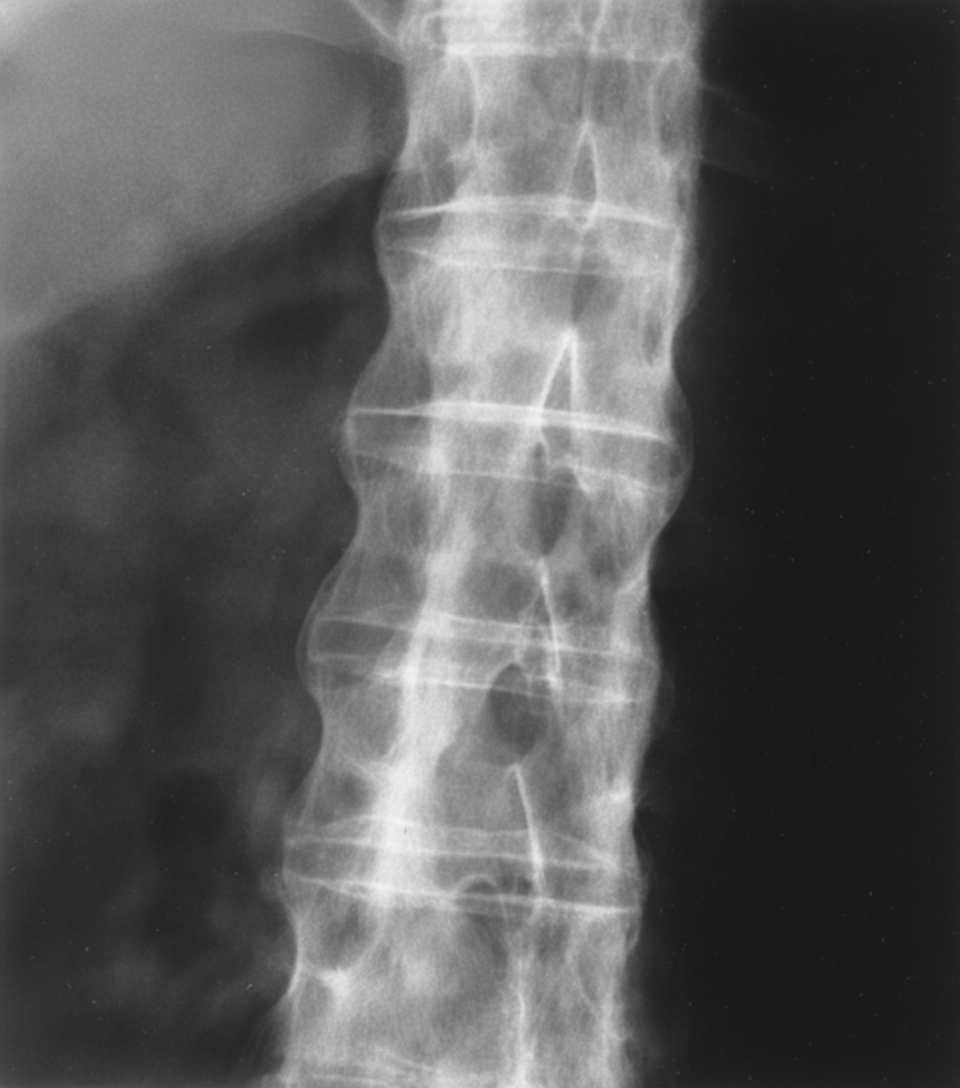

A 22-year-old man presents with low back pain and stiffness, which have progressively worsened over several months. He also reports nocturnal stiffness and hip pain. Physical examination reveals paravertebral muscle tenderness and limited lumbar spine flexion. Radiographic findings of the lumbar spine are shown. What is the most likely diagnosis?

Explanation: ***Ankylosing spondylitis*** - Progressive **low back pain** and **stiffness** with **nocturnal symptoms** in a young male, along with **limited lumbar spine flexion**, are classic features of ankylosing spondylitis. - Radiographic findings typically show **sacroiliac joint involvement** and may progress to the characteristic **"bamboo spine"** appearance due to syndesmophyte formation. *Reiter syndrome* - Also known as **reactive arthritis**, typically follows **genitourinary** or **gastrointestinal infections** and presents with the classic triad of **arthritis**, **conjunctivitis**, and **urethritis**. - Usually affects **peripheral joints** asymmetrically rather than causing progressive spinal involvement with characteristic radiographic changes. *Marfan syndrome* - A **connective tissue disorder** characterized by **tall stature**, **arachnodactyly**, **lens dislocation**, and **cardiovascular abnormalities** like aortic root dilatation. - Does not typically cause **inflammatory back pain** or the specific radiographic spinal changes seen in spondyloarthropathies. *Rheumatoid arthritis* - Primarily affects **small joints** of the hands and feet in a **symmetric pattern**, with morning stiffness that improves throughout the day. - Associated with **positive rheumatoid factor** and **anti-CCP antibodies**, and does not typically cause the characteristic spinal fusion seen in ankylosing spondylitis.